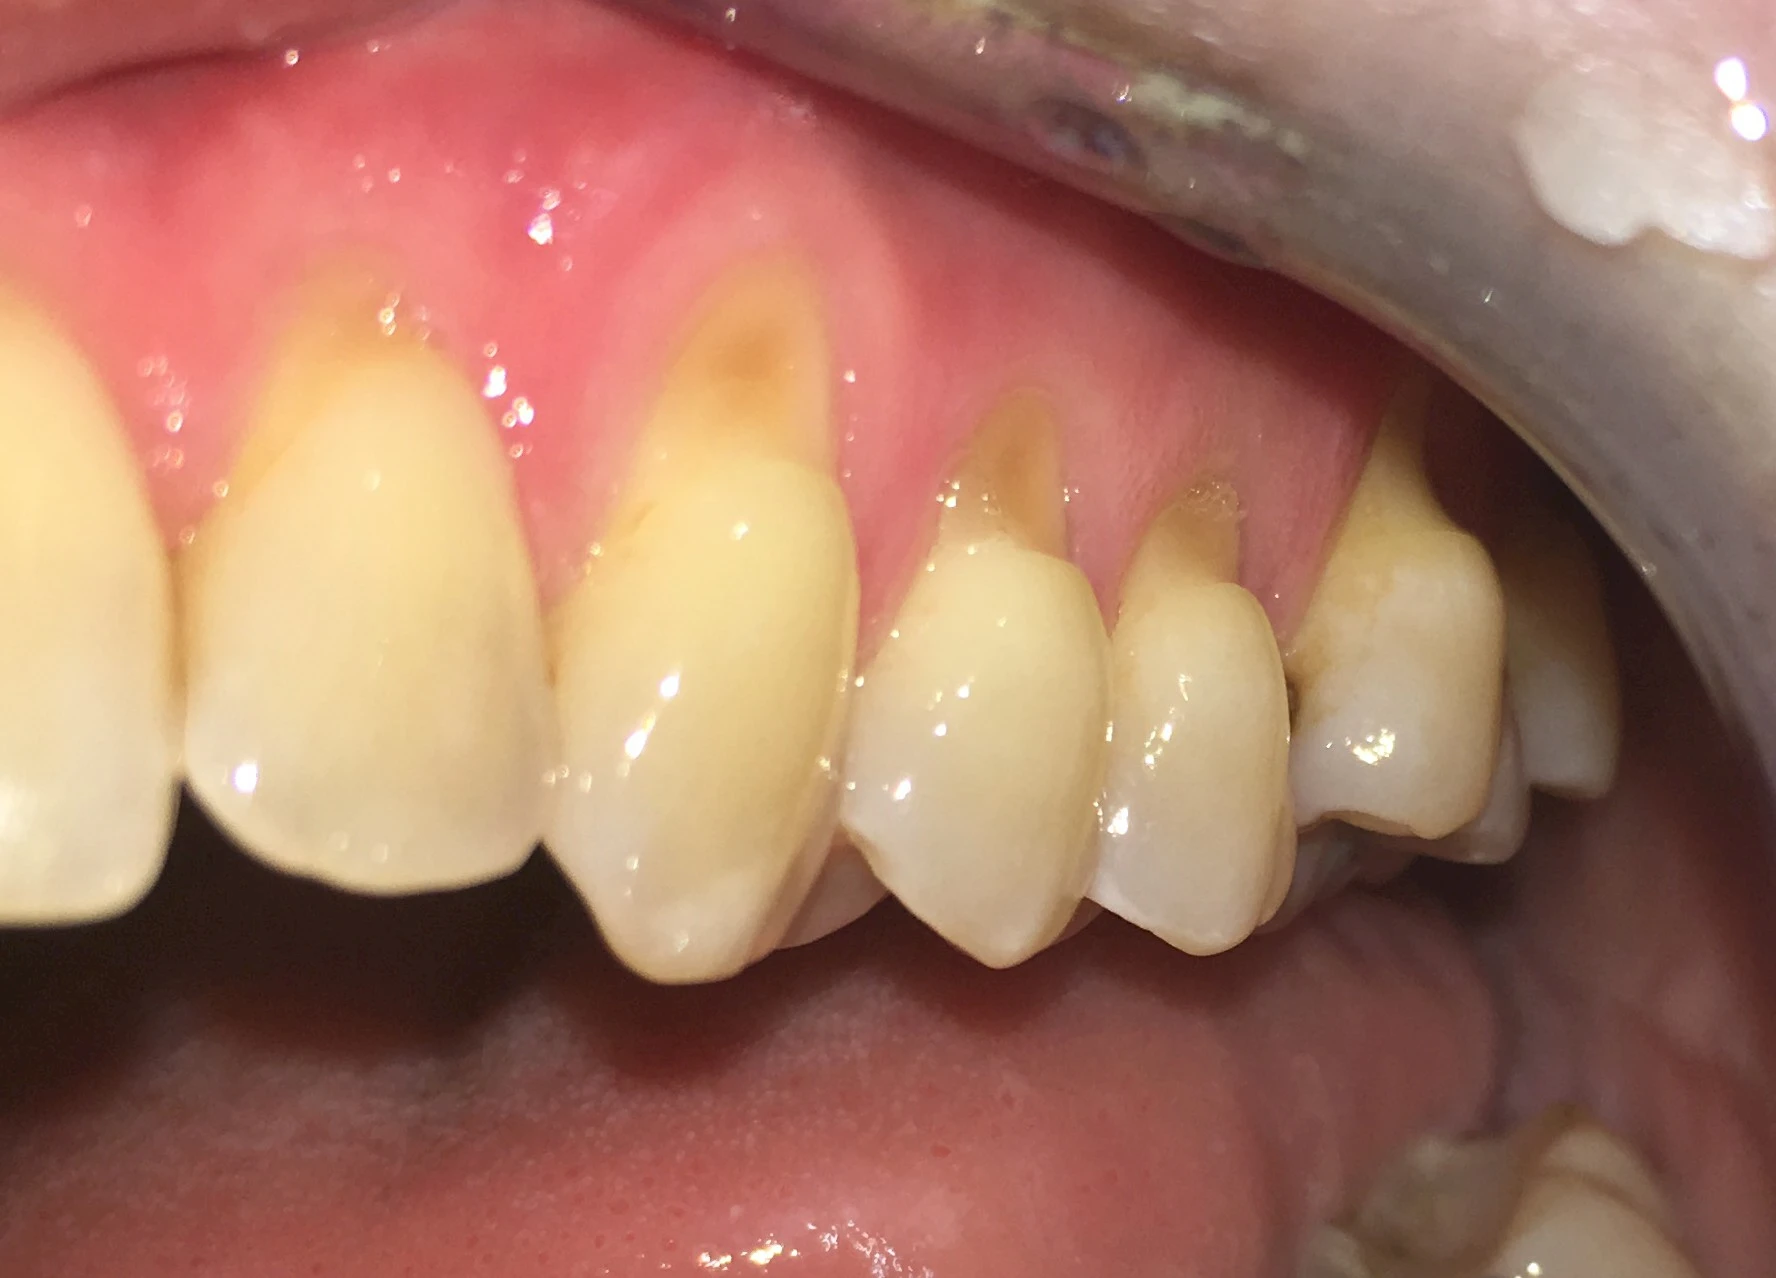

Keilförmiger Defekt

Eine Sonderform sind sogenannte keilförmige Defekte im Bereich der Zahnhälse. Hier geht man davon aus, dass Knirschen und Pressen in Kombination mit falschen Putzgewohnheiten (zu hoher Putzdruck, Verwendung von Zahnpasta mit hohen Abrasionswerten) eine Rolle spielen.